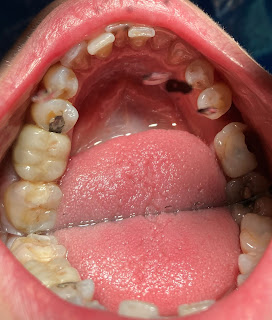

Mujer de 41 años, sin antecedentes médicos de interés, pero con obturaciones previas en: 16, 15, 25, 36 y 45 y coronas en dientes: 13, 12, 11, 21, 22, 23 y 46. Tejidos periodontales sanos.

Acude a consulta del máster de endodoncia, remitida por nuestros compañeros de la Policlínica, debido a molestias en el diente 47 desde hace un mes junto a mucha sensibilidad al frío.

Al llegar a la cámara pulpar observamos la siguiente conformación en forma triángular, presentando la raíz mesial dos conductos independientes (MV y ML) tipo I de Vertucci y la raíz distal un único conducto tipo I de Vertucci.